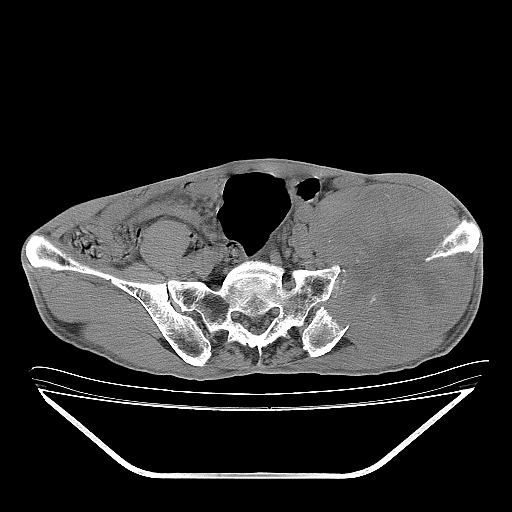

以下是引用天南地北在2007-10-4 18:01:00的发言:[br][br]考虑左髂部恶性肿瘤(溶骨性骨质破坏+软组织肿块影+残留骨质);以滑膜肉瘤可能性大。[br]建议穿刺活检

以下是引用liuyue在2007-10-4 23:38:00的发言:[br]左髂部恶性肿瘤,建议穿刺活检,或先做肺部检查,除外肺癌转移之可能。